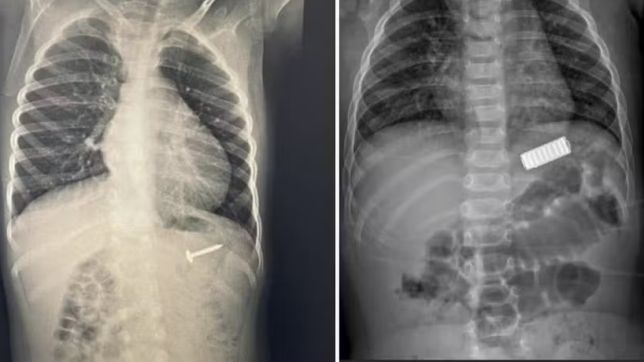

De ingestão de moedas a queimaduras: riscos de acidentes domésticos aumentam nas férias